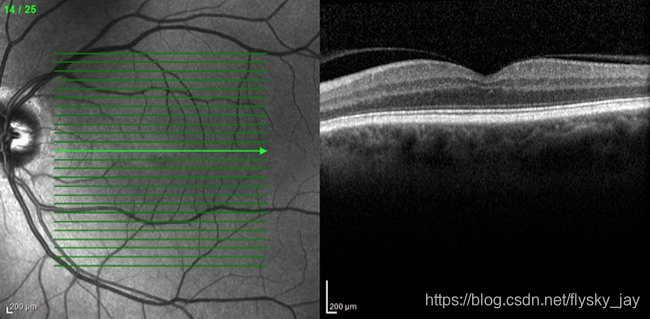

Optical Coherence Tomography (OCT) is a non-invasive imaging technique used to evaluate the retina. The image is acquired using laser light to scan the retina and results in an image that shows the retinal layers in great detail. When looking at an OCT scan we see it as if the retina were cut in half and seen from the side. This allows all the layers to be visualized all the way back to the wall of the eye, the sclera.

光学相干断层扫描(OCT)是一种无创的视网膜评估技术,利用激光光扫描视网膜,能详细显示视网膜各层。OCT对于涉及黄斑部的疾病特别有用,可帮助精确定位视网膜损伤,辅助诊断和治疗进程评估,如老年黄斑变性和糖尿病黄斑水肿。此外,OCT还能用于评估手术需求,如Epiretinal Membranes和Macular Holes的情况。